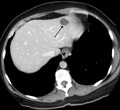

Capillary hemangioma

The majority of IHs can be diagnosed by history and physical examination.[20] In rare cases, imaging (ultrasound with Doppler, magnetic resonance imaging), and/or cytology or histopathology are needed to confirm the diagnosis.[21][22] IHs are usually absent at birth or a small area of pallor, telangiectasias, or duskiness may be seen. A fully formed mass at birth usually indicates a diagnosis other than IH. Superficial hemangiomas in the upper dermis have a bright-red strawberry color, whereas those in the deep dermis and subcutis, deep hemangiomas, may appear blue and be firm or rubbery on palpation. Mixed hemangiomas can have both features.[20] A minimally proliferative IH is an uncommon type that presents with fine macular telangiectasias with an occasional bright-red, papular, proliferative component. Minimally proliferative IHs are more common in the lower body.[23]

A precise history of the growth characteristics of the IH can be very helpful in making the diagnosis. In the first 4 to 8 weeks of life, IHs grow rapidly with primarily volumetric rather than radial growth. This is usually followed by a period of slower growth that can last 6–9 months, with 80% of the growth completed by 3 months. Finally, IHs involute over a period of years.[24] The exceptions to these growth characteristics include minimally proliferative His, which do not substantially proliferate[23] and large, deep IHs in which noticeable growth starts later and lasts longer.[24] If the diagnosis is not clear based on physical examination and growth history (most often in deep hemangiomas with little cutaneous involvement), then either imaging or histopathology can help confirm the diagnosis.[21][25] On Doppler ultrasound, an IH in the proliferative phase appears as a high-flow, soft-tissue mass usually without direct arteriovenous shunting. On MRI, IHs show a well-circumscribed lesion with intermediate and increased signal intensity on T1- and T2-weighted sequences, respectively, and strong enhancement after gadolinium injections, with fast-flow vessels.[21] Tissue for diagnosis can be obtained via fine-needle aspiration, skin biopsy, or excisional biopsy.[26] Under the microscope, IHs are unencapsulated aggregates of closely packed, thin-walled capillaries, usually with endothelial lining. Blood-filled vessels are separated by scant connective tissue. Their lumina may be thrombosed and organized. Hemosiderin pigment deposition due to vessel rupture may be observed.[27] The GLUT-1 histochemical marker can be helpful in distinguishing IHs from other items on the differential diagnosis, such as vascular malformations.[22]